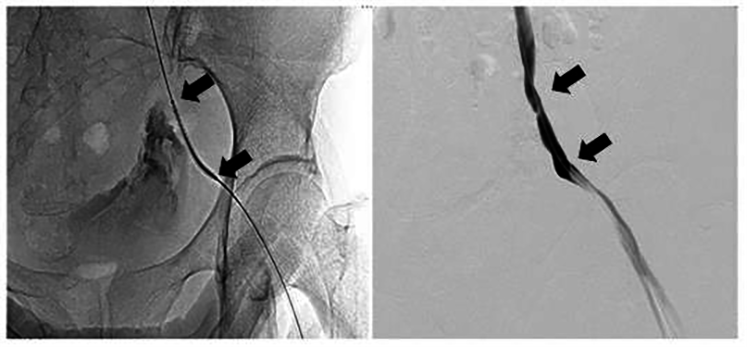

Fig. 3.A covered stent was introduced using a guide wire. Distal angiography showed no contrast agent overflow (between arrows).